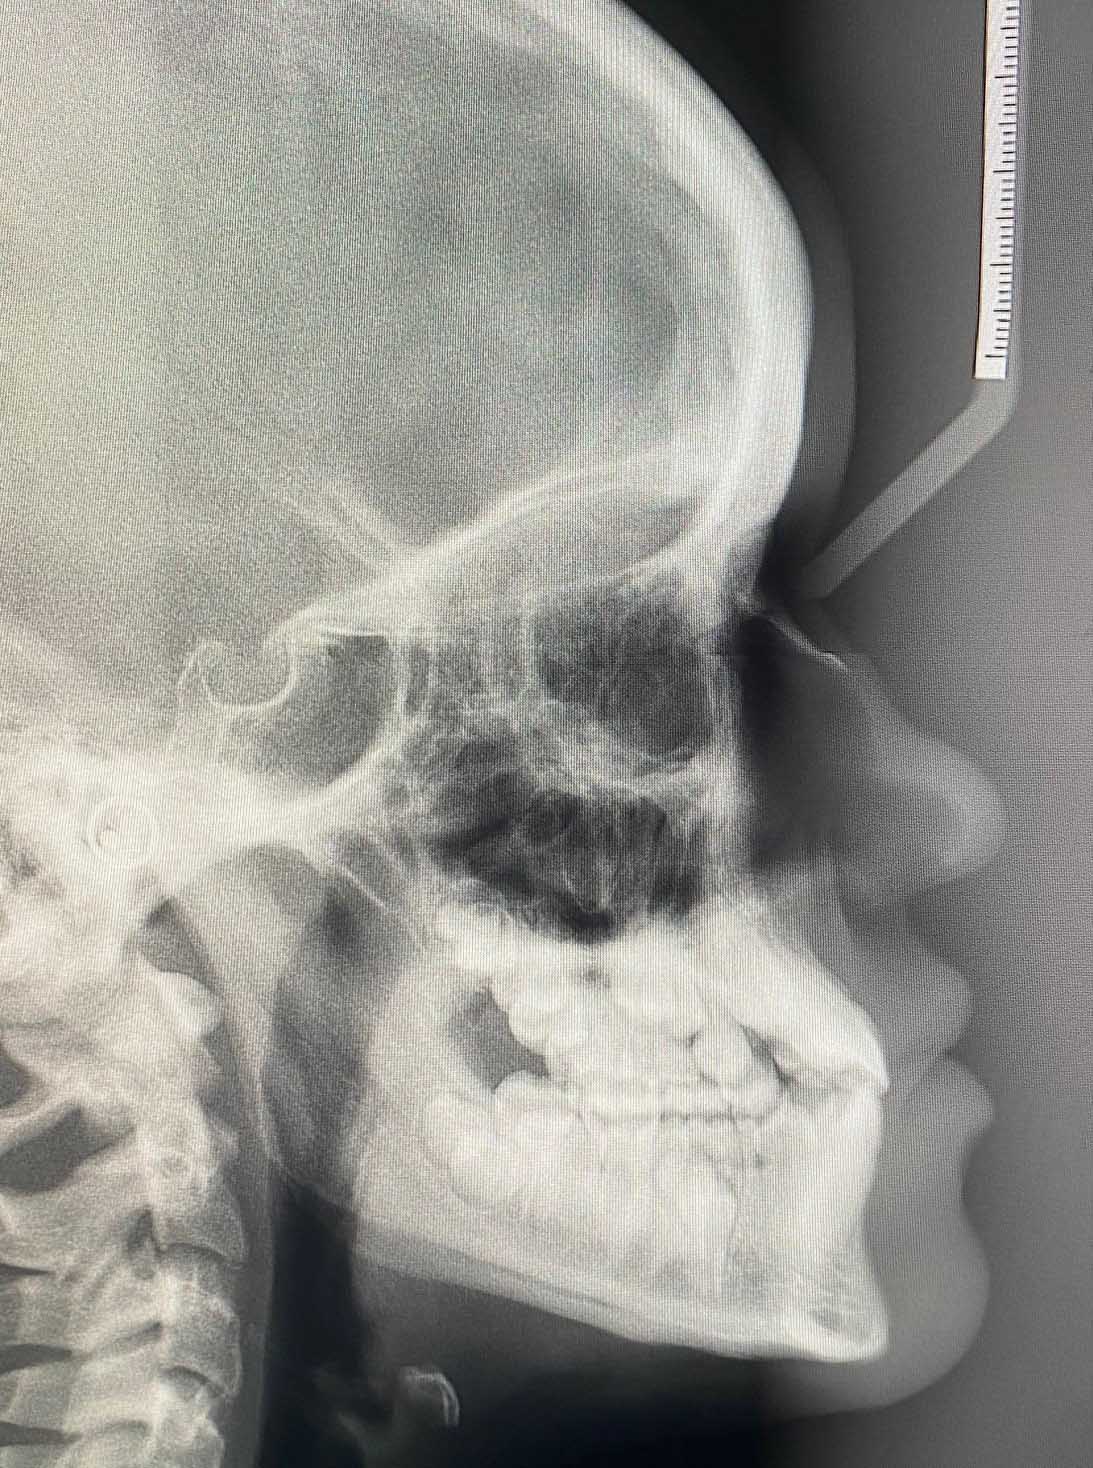

Oppstart med dokumentasjon

Vi tar nødvendige røntgenbilder, foto og kliniske modeller/skanninger. Dette danner det faglige grunnlaget for en individuell behandlingsplan og sikrer korrekt beregning av refusjon fra Helfo.